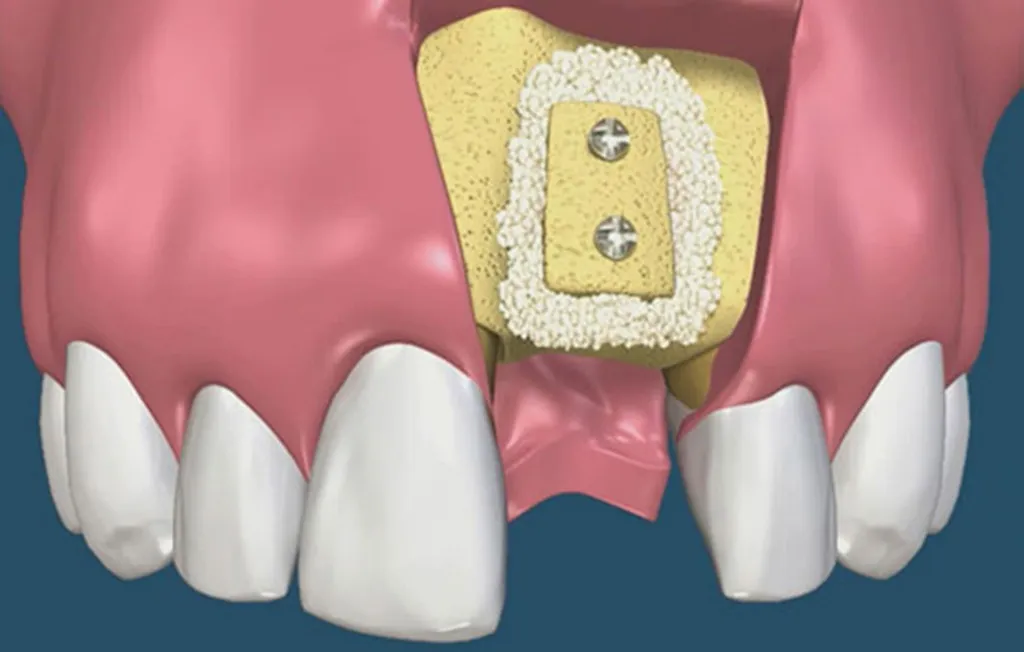

Ghép xương hàm là kỹ thuật điều trị bổ sung cần thiết trước khi cấy ghép implant. Nó được thực hiện khi mật độ xương hàm tại

Hiện nay, kỹ thuật cấy ghép implant là phương pháp nha khoa phổ biến nhất. Tuy nhiên, để thực hiện được việc cấy ghép an toàn thì